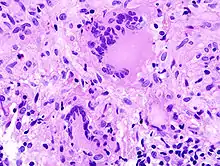

Kriterien der Malignität

- Histologisch: Nekrosen, Kapillarisierung (Neoangiogenese), Aufhebung der normalen Histologie.

- Zytologisch: Polymorphie, basophiles Cytoplasma, erhöhte Kern/Plasmarelation

- Nukleär: Polymorphie, Polychromasie, Hyperchromasie, Aneuploidie, (vergrößerte) Nukleolen, vermehrt Mitosen, atypische Mitosen, erhöhter Proliferationsindex (Ki-67 = MIB-1).